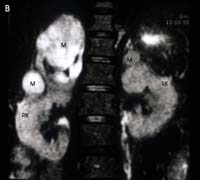

รูปที่ 13 แสดง Pheochromocytoma ในผู้ป่วยหญิงอายุ 42 ปี

รูป B. ภาพ MRI T2 ระนาบ coronal แสดงก้อนใหญ่ตะปุ่มตะป่ำข้างขวา และก้อนเล็กข้างซ้าย ซึ่ง singal intensity ไม่เท่ากัน

(M = adrenal mass, RK = right kidney, LK = left kidney)